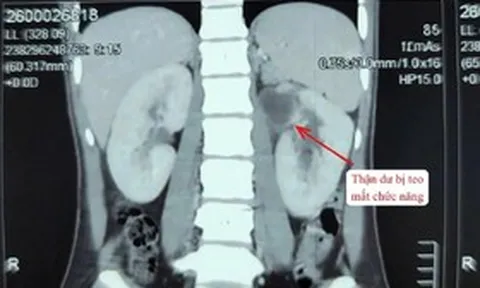

Đây là trường hợp bệnh lý phức tạp khi người bệnh không chỉ mang khối u xơ tử cung khổng lồ (tương đương 1 trường hợp song thai 36 - 38 tuần) mà còn đối mặt với nguy cơ thuyên tắc phổi và tai biến tim mạch rất cao trong thời gian phẫu thuật.

Ê-kíp phẫu thuật đối mặt với việc khối u dính chặt vào phúc mạc, mạc nối và các quai ruột non. Hệ thống mạch máu nuôi u tăng sinh mạnh mẽ với những mạch máu có đường kính lên tới 7 mm.

Nhờ sự phối hợp chặt chẽ giữa phẫu thuật viên và ê-kíp gây mê hồi sức, đặc biệt là việc theo dõi sát huyết động và nguy cơ thuyên tắc trong suốt quá trình mổ, ca phẫu thuật đã diễn ra an toàn. Tổng lượng máu mất khoảng 500 ml – con số thấp so với trường hợp u xơ kích thước lớn. Khối u được bóc tách hoàn toàn mà không gây tổn thương các cơ quan lân cận. Đáng chú ý, tử cung của bệnh nhân được bảo tồn thành công.